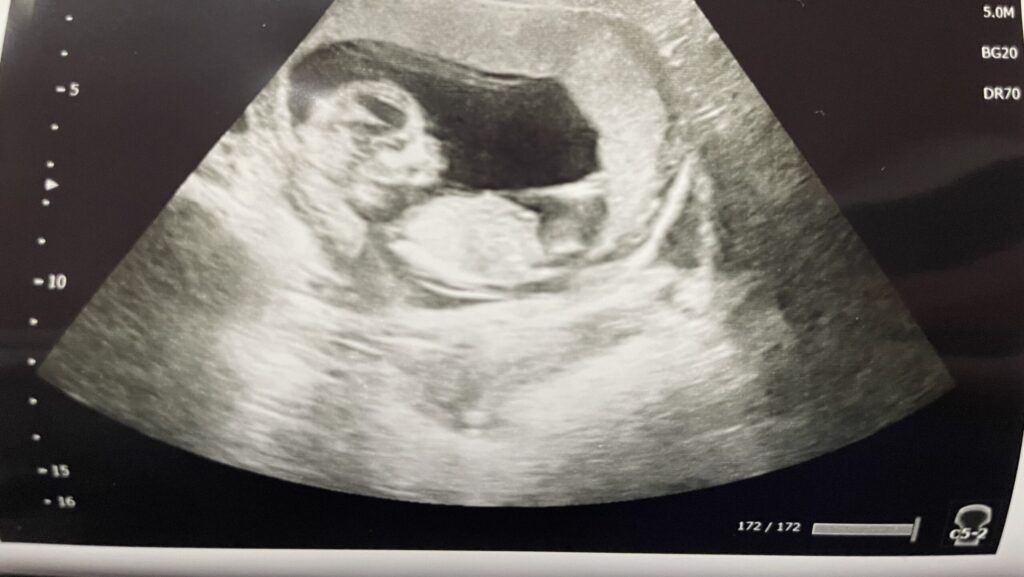

それから、妊婦健診にお決まりの胎児エコー👶

流産の壁と言われる12週目でしたので、ちゃんと生きているか心配でしたが…

全く動かなかったものの、元気そうにしていました🥹

寝てるんだろうけど、あまりにも動かないから心臓の音が聞こえるまでハラハラでした💦

前のエコーのときとは頭の向きも変わってて、中で相当動いてたんだろうなぁとは予測できます😅